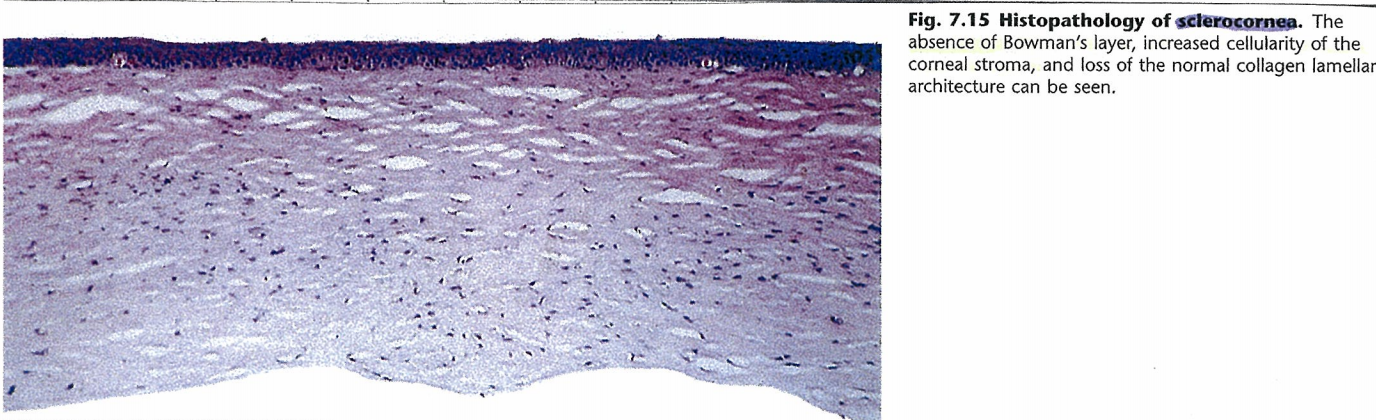

공막화각막에선느 각막의 특징적인 보우만막이없으며, 각막기질의 밀도가 높아지면서,

각막기질이 가지는 특징적인 콜라겐 구조가 깨지면서, 불투명해집니다.